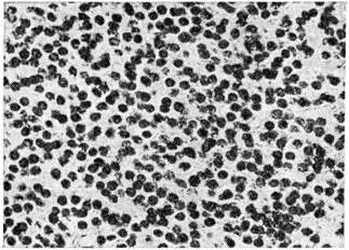

Микроскопически различают Олигодендроглиома типической и атипической структуры. Типические Олигодендроглиома состоят из густо и равномерно расположенных клеток со скудной цитоплазмой и ядрами сферической формы с нежными глыбками хроматина и чётким ядрышком (рисунок 2), напоминающих обычный олигодендроглиоцит. Нередко ткань опухоли приобретает мелкоячеистую (напоминающую соты) структуру, в центре ячейки располагается по нескольку ядер, окружённых светлой неокрашенной зоной (рисунок 3). Иногда в ткани Олигодендроглиома наряду с клетками, напоминающими олигодендроглиоциты, обнаруживают пучки веретенообразных клеток с отростками и ядрами вытянутой формы. В ряде случаев в Олигодендроглиома встречаются участки астроцитомы (смотри полный свод знаний), которая содержит глиальные волокна, импрегнирующиеся методом Рамон-и-Кахаля. Подобные опухоли диагностируются как олигодендроастроцитомы.. В Олигодендроглиома имеется небольшое или умеренное количество мелких сосудов. Характерным является отложение солей извести в ткани опухоли, сосудах и прилежащем мозговом веществе. Нередки мелкие кисты.